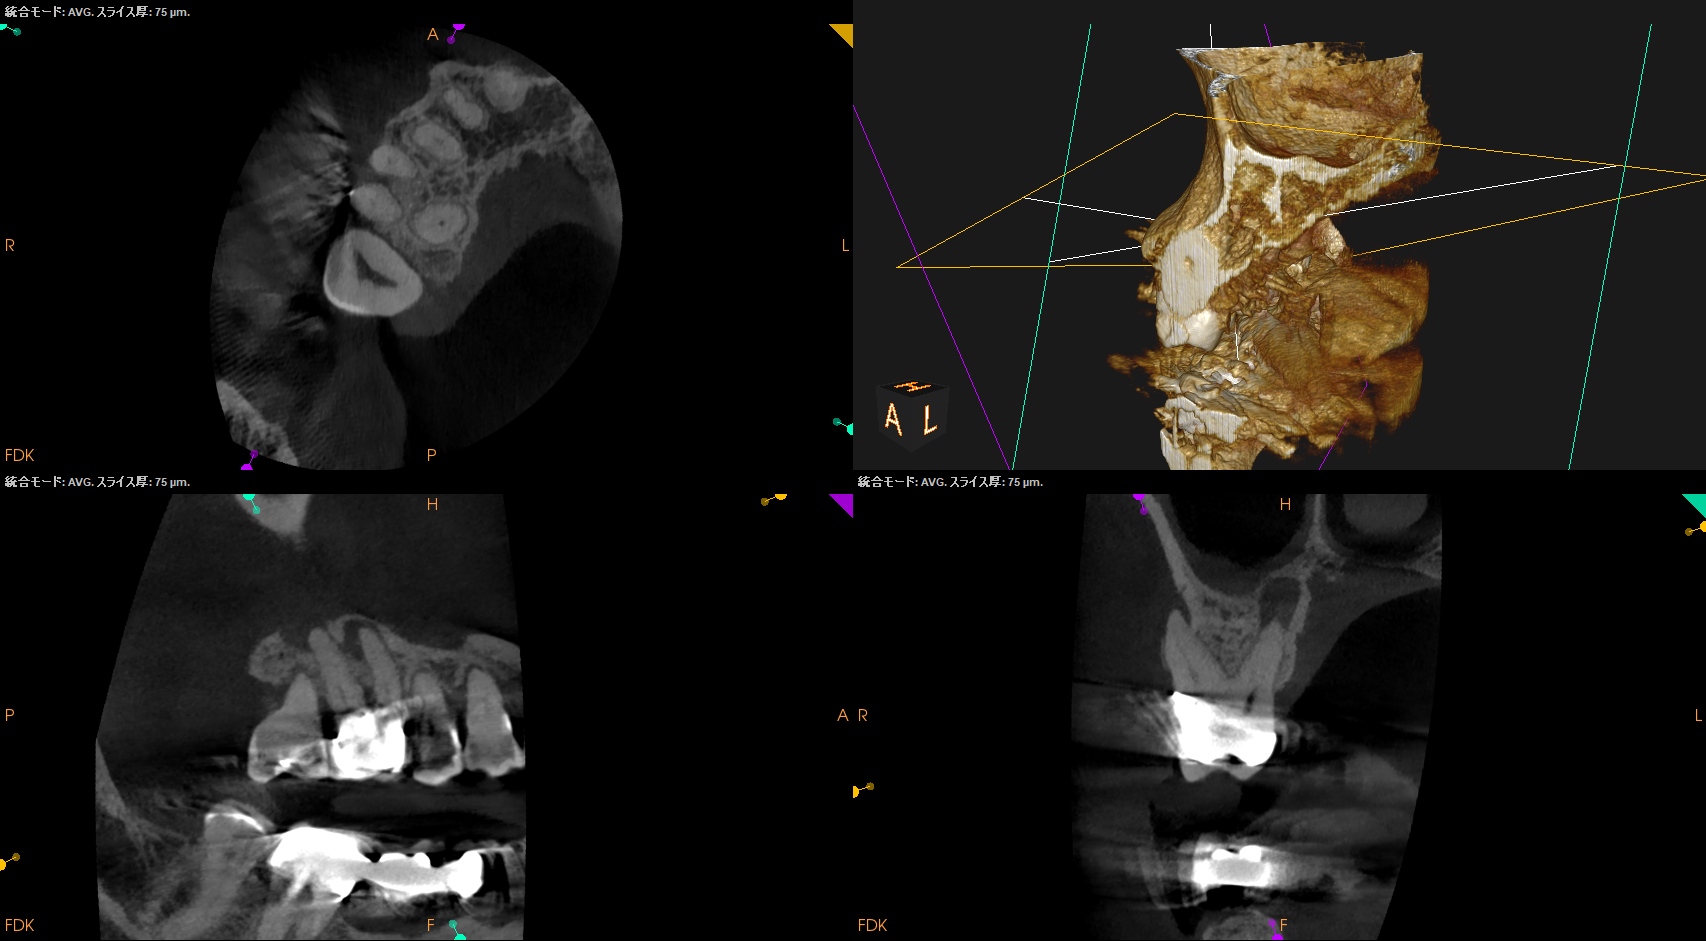

#3 RCT 1yr recall(2026.1.5)

DBの歯槽骨はまだ回復中(Healiing)だが臨床症状は消失した。

ということでまた来年も経過を見ることとなった。